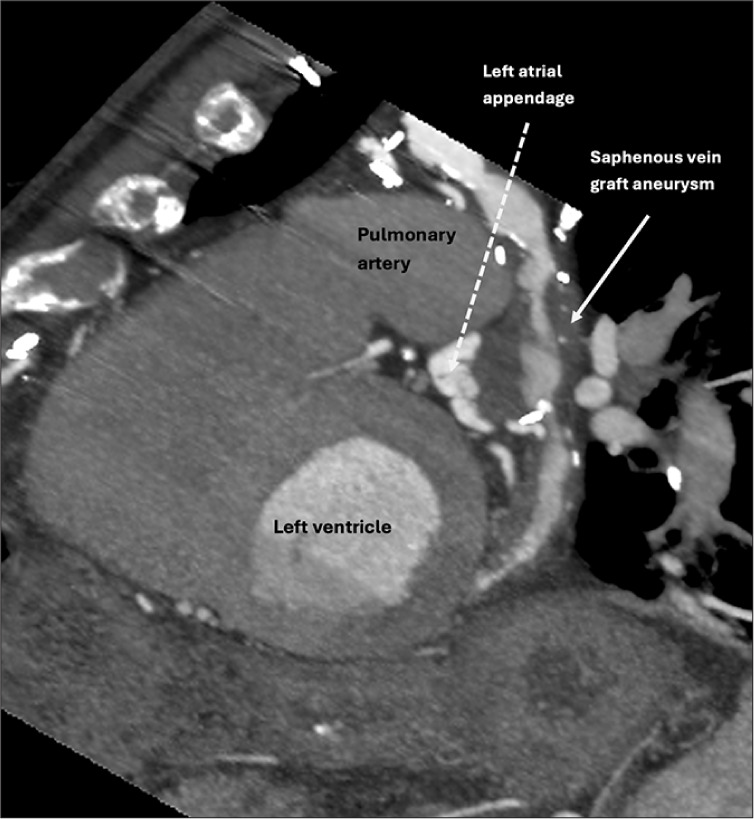

Saphenous vein graft aneurysm (SVGA) is a rare but potentially life-threatening complication of coronary artery bypass grafting (CABG). Its incidence is likely underreported due to asymptomatic cases and undiagnosed acute events. While SVGAs are more commonly associated with right atrial compression, presentation as a left atrial mass is rare. We present the case of an 85-year-old man with a history of CABG, who was incidentally found to have a left atrial appendage (LAA) density on a computed tomography (CT) chest, abdomen, and pelvis performed for unrelated symptoms of back pain and constipation. The density was initially suspected to be an LAA thrombus. However, a dedicated cardiac CT with delayed-phase imaging revealed a largely thrombosed aneurysmal saphenous vein graft to the obtuse marginal artery, which indented the LAA, mimicking an intracardiac mass. This case underscores the critical role of multimodality imaging, particularly cardiac CT, in differentiating vascular aneurysms from true intracardiac masses. Given the patient's asymptomatic status, conservative management with close follow-up was pursued. This case adds to the limited literature on SVGAs mimicking left atrial pathology and highlights the importance of recognizing this rare entity to avoid unnecessary interventions. It also emphasizes the evolving role of cardiac CT as a noninvasive, high-yield diagnostic tool for complex post-CABG anatomical assessments.

Abstract Image